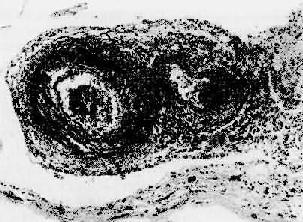

红斑性狼疮之脾病变

图4-12 红斑性狼疮之脾病变

脾小体中央细动脉壁呈洋葱皮样结构